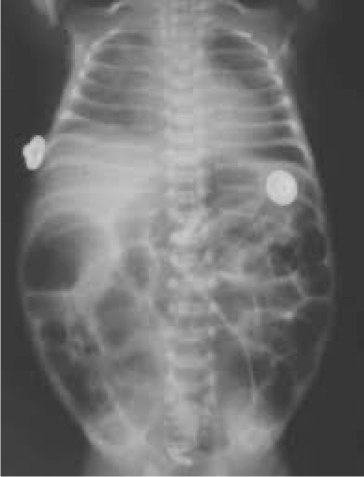

A preterm infant born at 25 weeks gestation is now 6 weeks old. The infant has been stable for the past few weeks, breathing in room air, and receiving full enteral feedings that consist of fortified maternal breast milk and some formula supplementation. Yesterday, the infant had a few large gastric residuals with feeding but was otherwise well. Today, you were called for a new onset of apneic spells, increased abdominal distension, poor urine output, lethargy, and hypothermia.

What is your spot diagnosis? necrotizing enterocolitis

- Dilated loops,

- thickened bowel walls,

- pneumatosis intestinalis (air in intestinal walls),

- pneumoperitoneum; indicate perforation (emergency requiring surgical intervention),

- portal gas (present in the portal venous system,

- considered to be a poor prognostic sign).

inflamed, necrosis ⇒ Perforation everywhere

dark circles air in intestinal wall

Air in portal gas